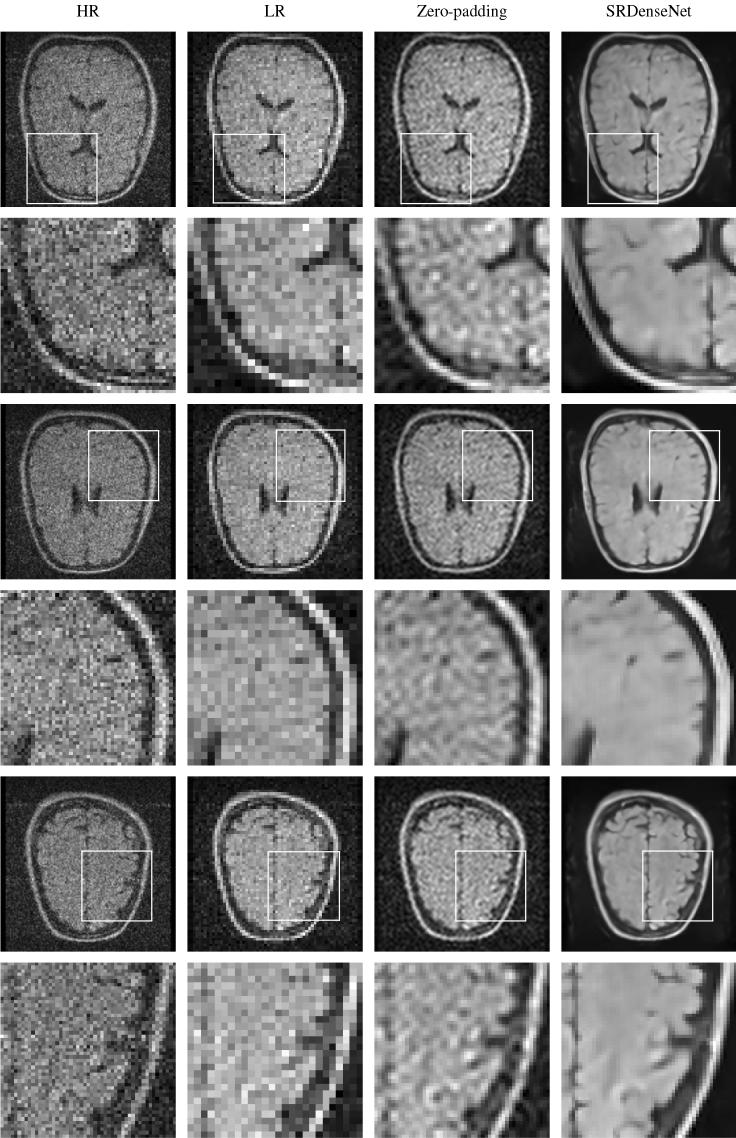

Low-field MRI scanners are significantly less expensive than their high-field counterparts, which gives them the potential to make MRI technology more accessible all around the world. In general, images acquired using low-field MRI scanners tend to be of a relatively low resolution, as signal-to-noise ratios are lower. The aim of this work is to improve the resolution of these images. To this end, we present a deep learning-based approach to transform low-resolution low-field MR images into high-resolution ones. A convolutional neural network was trained to carry out single image super-resolution reconstruction using pairs of noisy low-resolution images and their noise-free high-resolution counterparts, which were obtained from the publicly available NYU fastMRI database. This network was subsequently applied to noisy images acquired using a low-field MRI scanner. The trained convolutional network yielded sharp super-resolution images in which most of the high-frequency components were recovered. In conclusion, we showed that a deep learning-based approach has great potential when it comes to increasing the resolution of low-field MR images.

低磁场磁共振成像扫描仪的价格明显低于高磁场磁共振成像扫描仪,这使得它们有可能使磁共振成像技术在全球范围内更容易获得。一般来说,使用低磁场磁共振成像扫描仪获得的图像的分辨率相对较低,因为信噪比较低。这项工作的目的是提高这些图像的分辨率。为此,我们提出了一种基于深度学习的方法,将低分辨率、低磁场的磁共振图像转换为高分辨率的图像。我们使用一对带有噪声的低分辨率图像及其无噪声的高分辨率图像对训练卷积神经网络进行单图像超分辨率重建,这些图像来自公开的 NYU fastMRI 数据库。然后,我们将这个网络应用于使用低磁场磁共振成像扫描仪获取的噪声图像。训练好的卷积网络生成了清晰的超分辨率图像,其中大部分高频成分都得到了恢复。总之,我们表明,基于深度学习的方法在提高低磁场磁共振图像的分辨率方面具有很大的潜力。